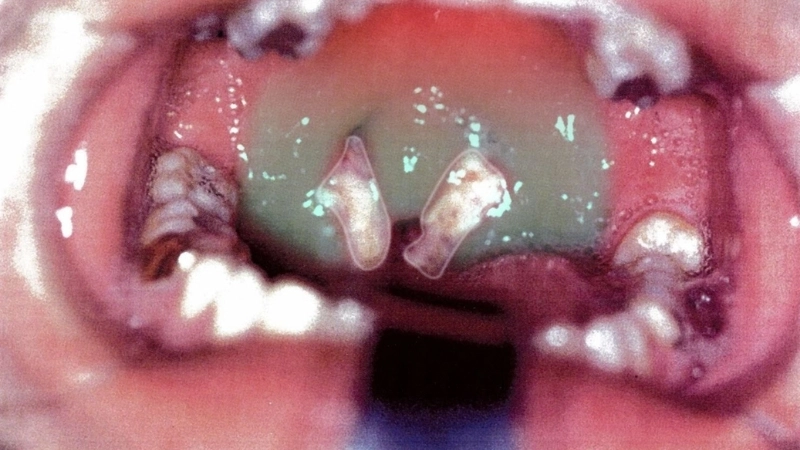

• Sore throat with white patches on the tonsils, occasionally causing difficulty swallowing and tender throat glands.

Image description of Infectious Mononucleosis (Glandular Fever)

Infectious Mononucleosis, also called glandular fever, is a contagious viral infection primarily caused by the Epstein-Barr virus. It often leads to fatigue, sore throat, and swollen lymph nodes, especially in adolescents and young adults.